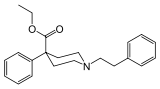

Phenylpiperidines

- Pethidine (meperidine)

The first fully synthetic opioid was meperidine (later demerol), found serendipitously by German chemist Otto Eisleb (or Eislib) at IG Farben in 1932.[228] Meperidine was the first opiate to have a structure unrelated to morphine, but with opiate-like properties.[199] Its analgesic effects were discovered by Otto Schaumann in 1939.[228] Gustav Ehrhart and Max Bockmühl, also at IG Farben, built on the work of Eisleb and Schaumann. They developed "Hoechst 10820" (later methadone) around 1937.[230] In 1959 the Belgian physician Paul Janssen developed fentanyl, a synthetic drug with 30 to 50 times the potency of heroin.[211][231] Nearly 150 synthetic opioids are now known.[228]